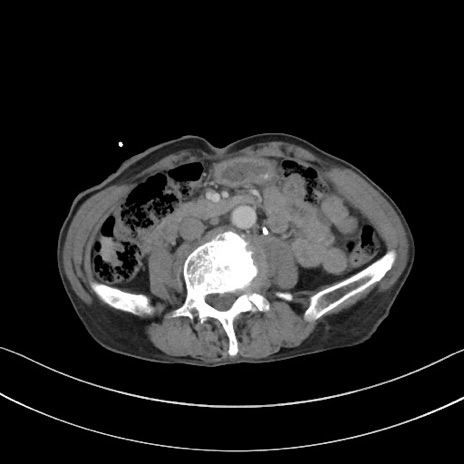

冠状断像

【症例】 70歳代男性

【主訴】右鼠径部腫瘤、疼痛

【現病歴】本日朝より上記主訴あり、受診。

【既往歴】膀胱癌にて膀胱全摘、両側尿管皮膚瘻

【データ】WBC 5600、CRP 0.56